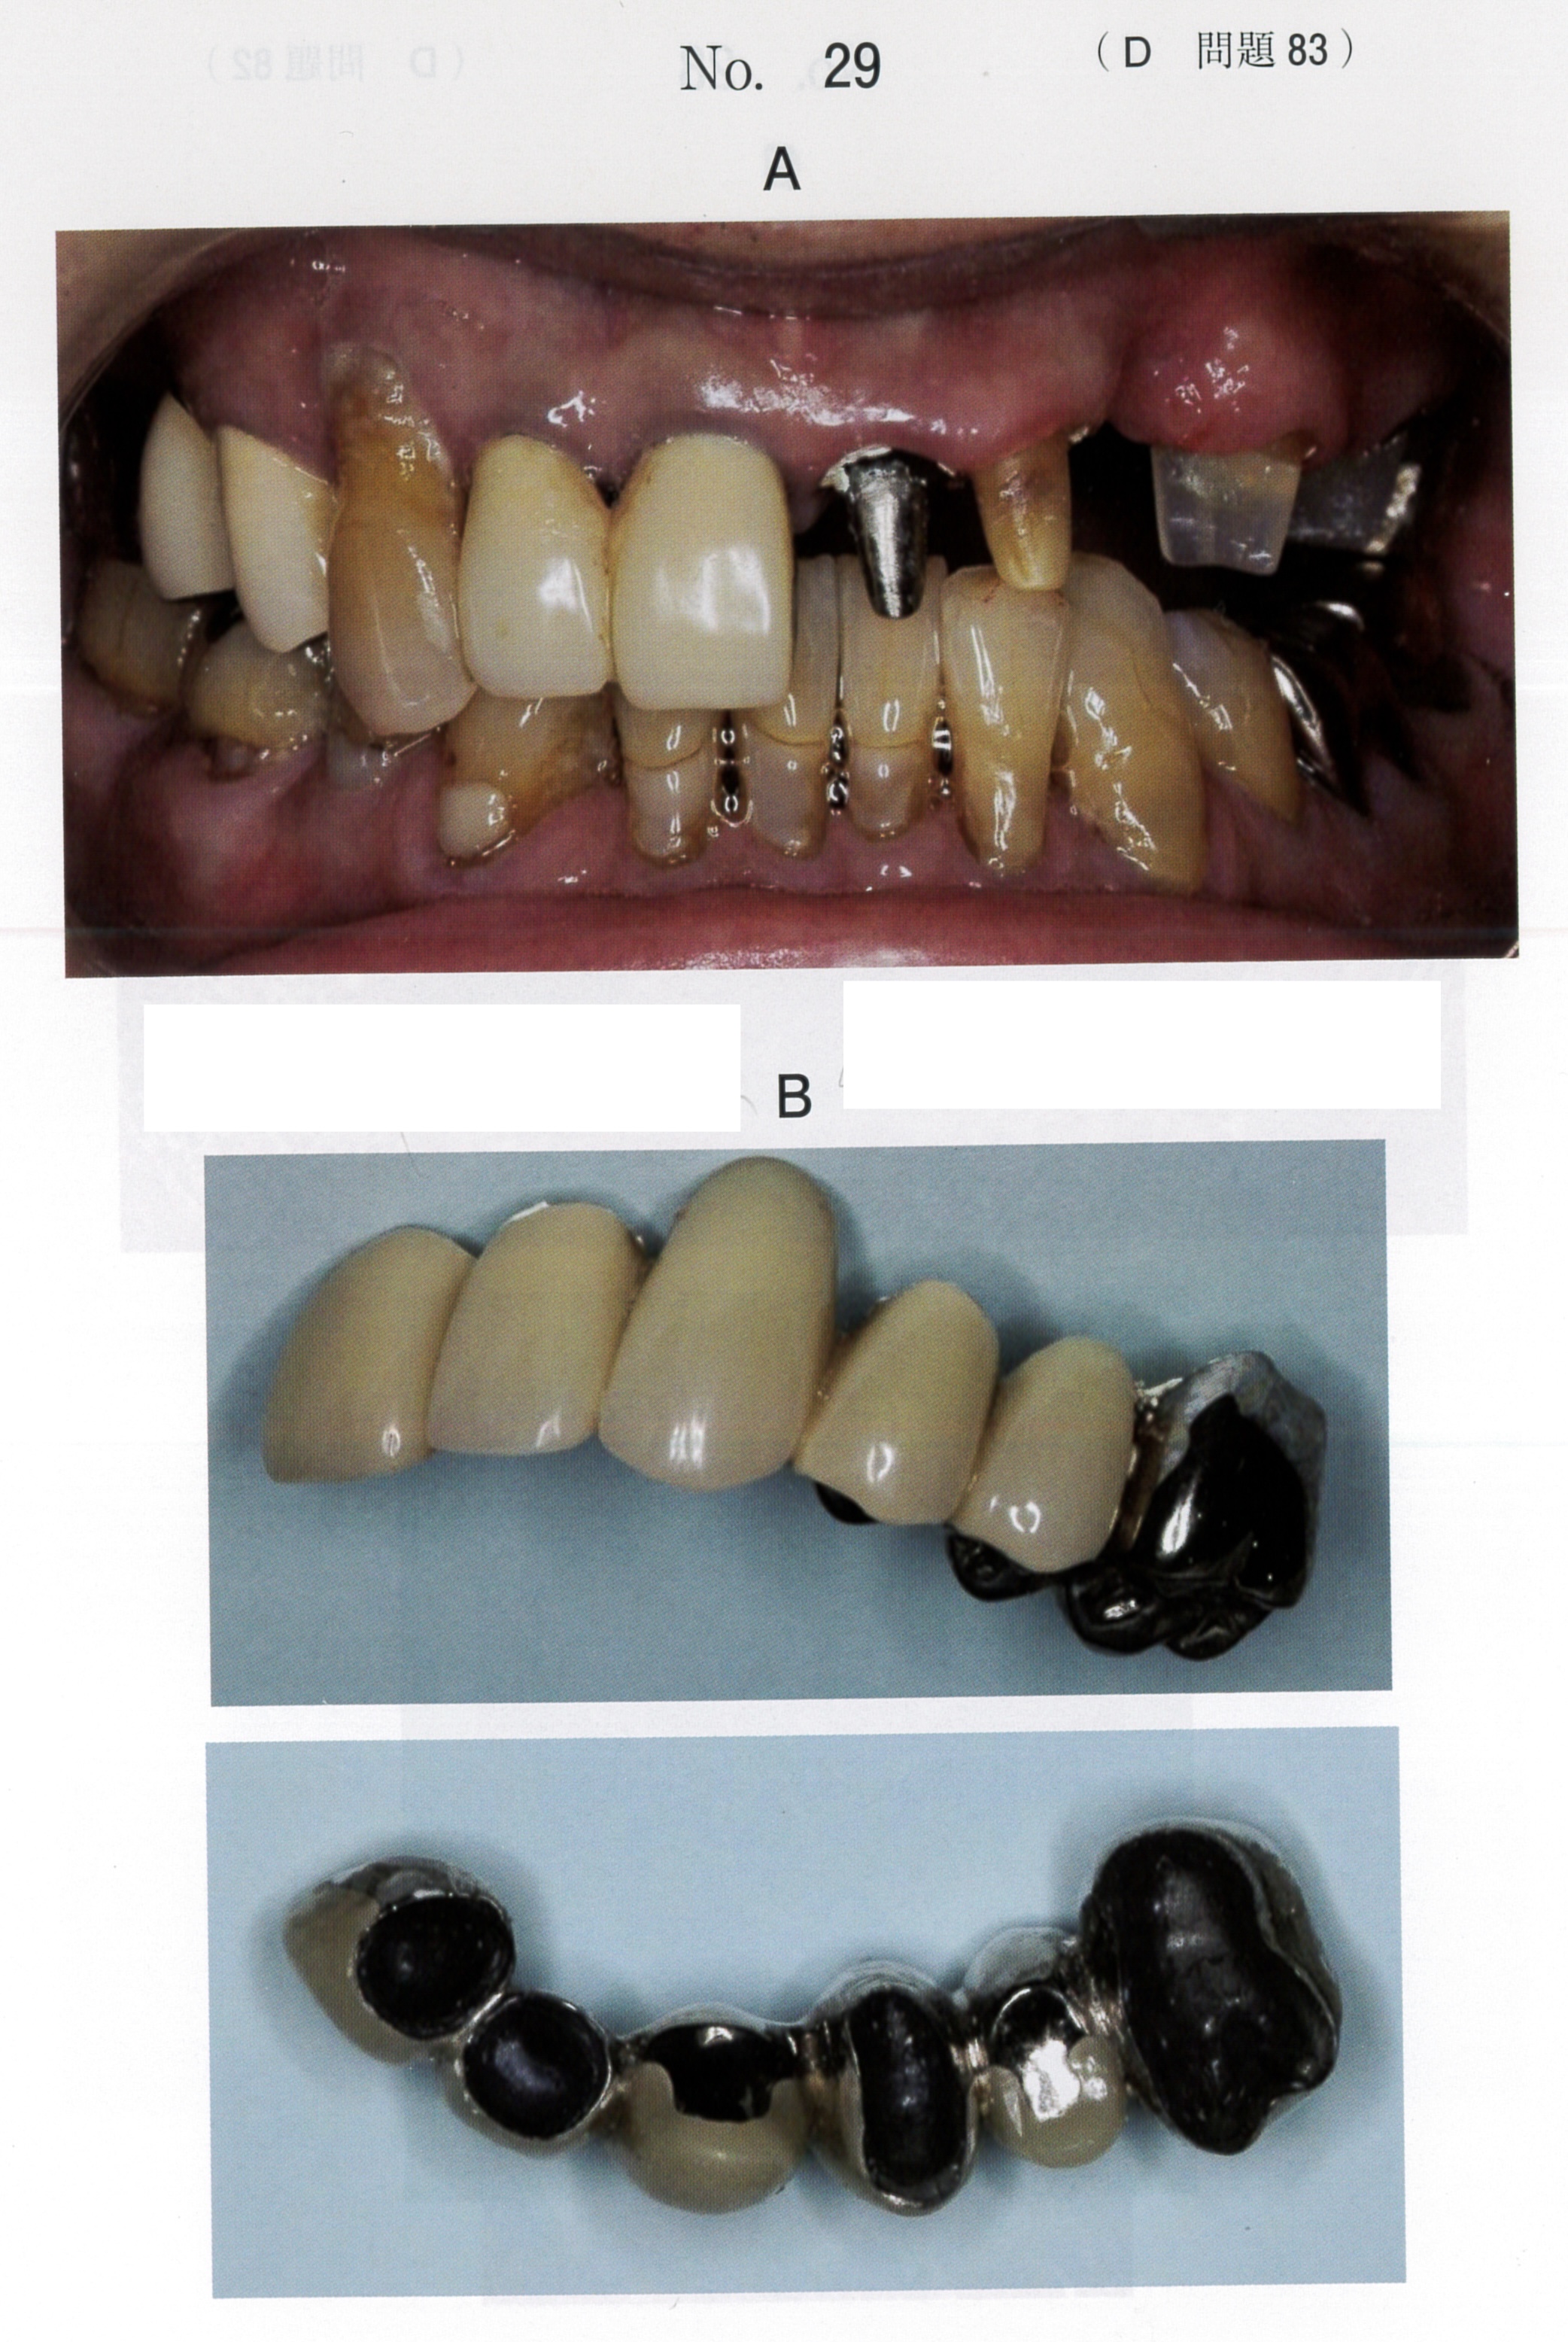

臨床医学に特化した国試対策テキスト。DES本校生限定資料 ① 小児歯科学(総括)P25② 臨床実技関連テキストP31③ 国試に出る症候群まとめP25状態)一切書き込み無し。裁断済み(神経質な方は控えてください)その他)ペット喫煙無し差し替え防止のため、返品返金不可。バラ売りの場合は、1冊子5000円とします。セット価格にしておきます。- タイトル: 国試に出る名詞整理まとめ- 内容: 臨床医学に関するテキストと資料- 形式: 印刷物- ページ数: 複数ページ- 対象: 医療従事者向け- 言語: 日本語ご覧いただきありがとうございます。